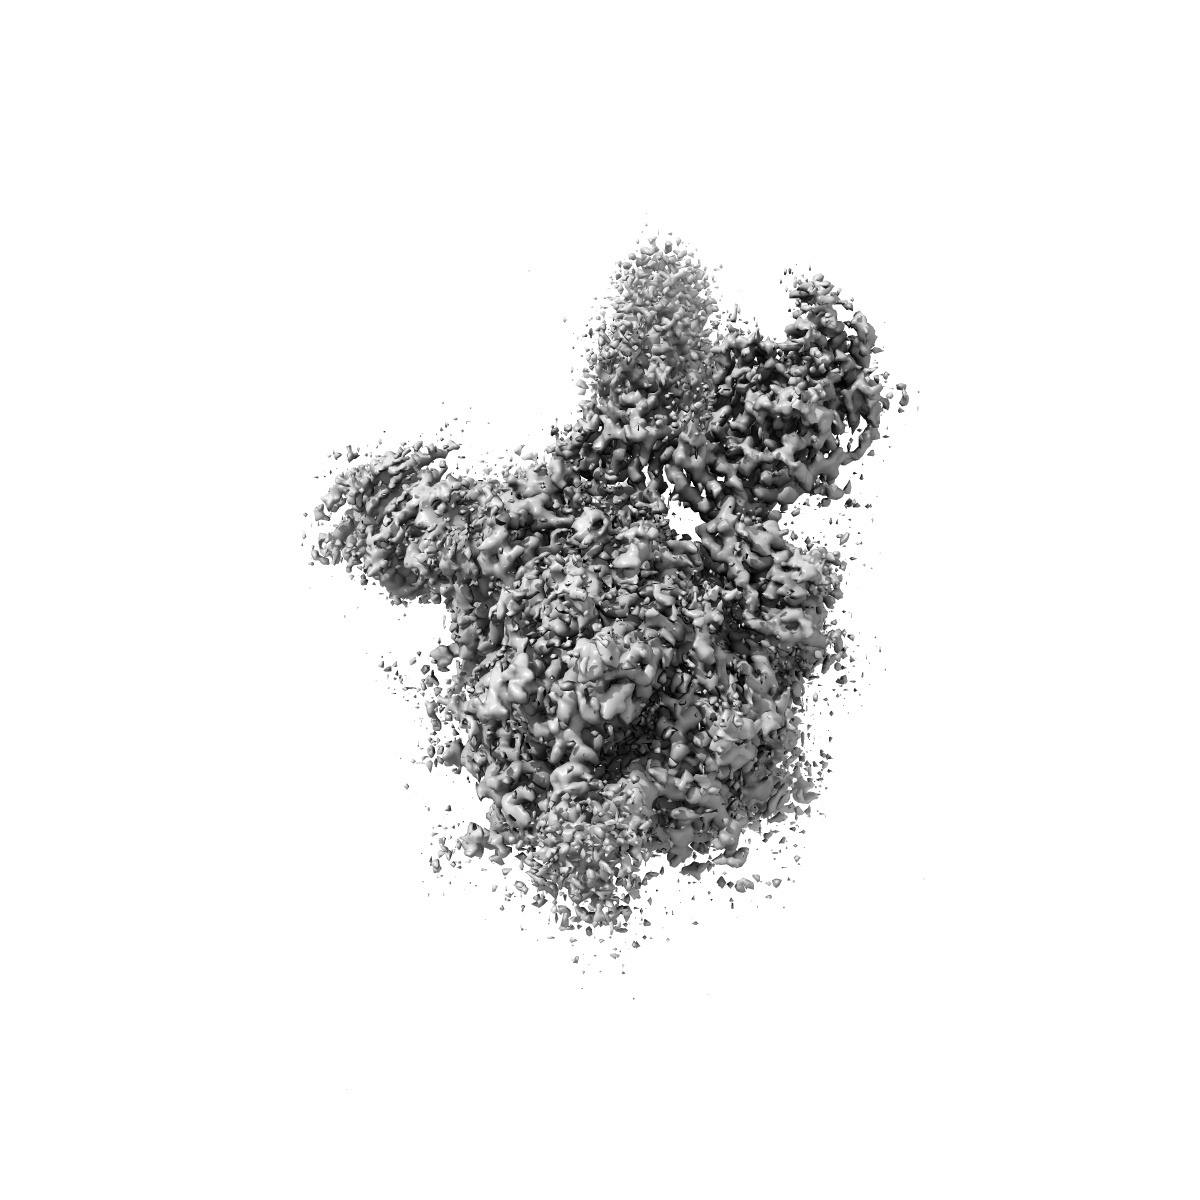

S protein of SARS-CoV-2 in complex bound with P5A-2G9

Single-particle2.7 Å

Sample: S protein of SARS-CoV-2 in complex bound with P2B-2G9

Fitted models: 7czt

Structural basis for bivalent binding and inhibition of SARS-CoV-2 infection by human potent neutralizing antibodies.

(2021) Cell Res , 31 , 517 - 525